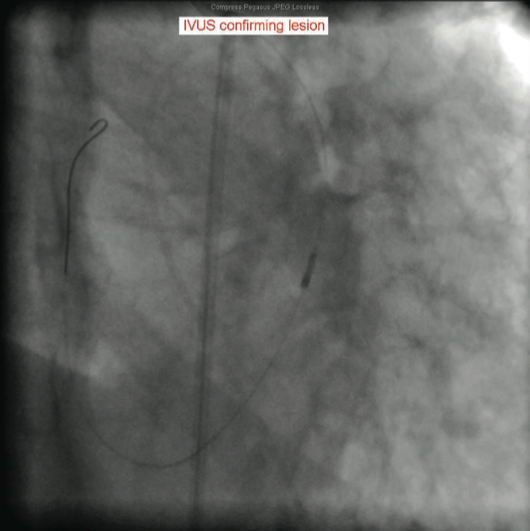

The catheterization and angiogram showed a patent left main coronary artery that bifurcated into the left anterior descending (LAD) and the left circumflex (LCX). The LAD had a mid 50% stenosis and the LCX was a large-sized vessel that gave off three obtuse marginal (OM) branches and continued distally into the right

side of the heart, filling the right coronary artery (RCA) from the distal end retrograde. The LCX had a mid 70-80% lesion that was confirmed by intravascular ultrasound (IVUS). The right coronary artery had no ostium and received retrograde filling via the LCX, continuing distally into the right myocardium. The LCX 80% mid stenosis was successfully revascularized with deployment of two drug-eluting stents. The patient was placed on post-procedure clopidogrel, simvastatin, beta blockers, and nitroglycerin.